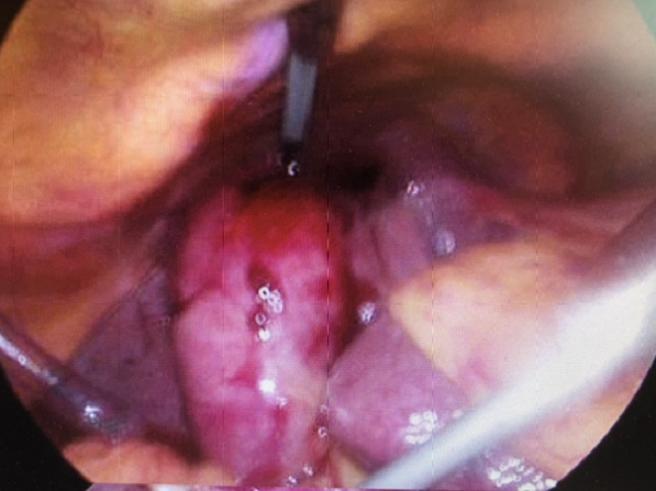

One weekend with three cruiseships in the bay, we had a woman in her seventies on a cruise of a lifetime with her husband. After leaving Antarctica she developed abdominal pain and diagnosis was gallbladder inflammation with pancreatitis.Being five days away from the Falklands she needed to stay in a hospital bed on the ship and upon arrival we performed emergency surgery and all went well. Staying on the ward some days after surgery I was informed she had to pay 4000GBP/night for the hospital bed on the cruiseship (20.000GBP for 5 nights).